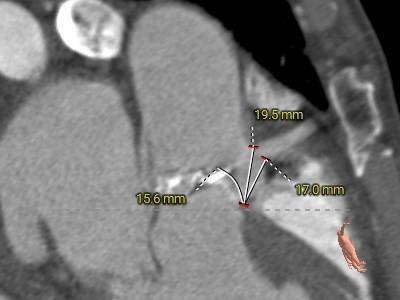

冠脉测量:

冠脉开口高度可,切线角度测量,未见冗长瓣叶。

左、右冠脉开口高度可,切线角度测量,未见冗长瓣叶;